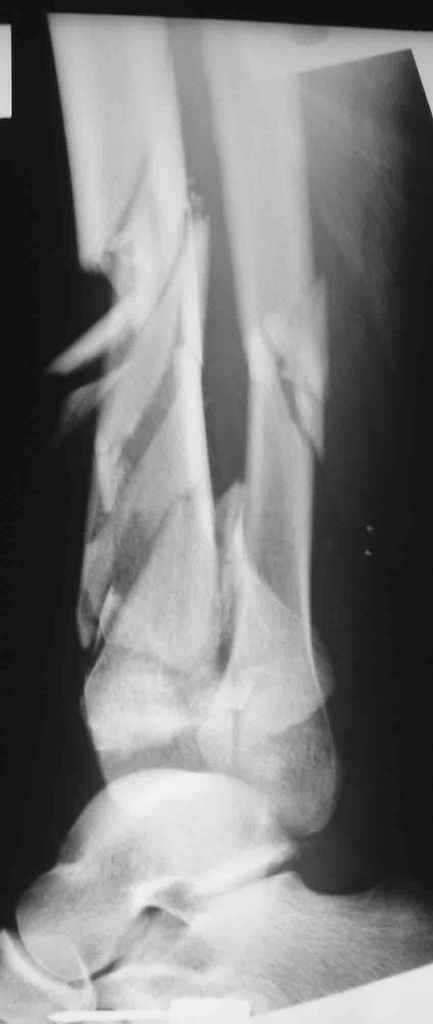

Re: Открытый оскольчатый внутрисуставной перелом дистального отдела большеберцовой кости

Смирнов Алексей 17 Март 2006, 21:51

Вот что получилось

7.jpg

27KB (28411 bytes)